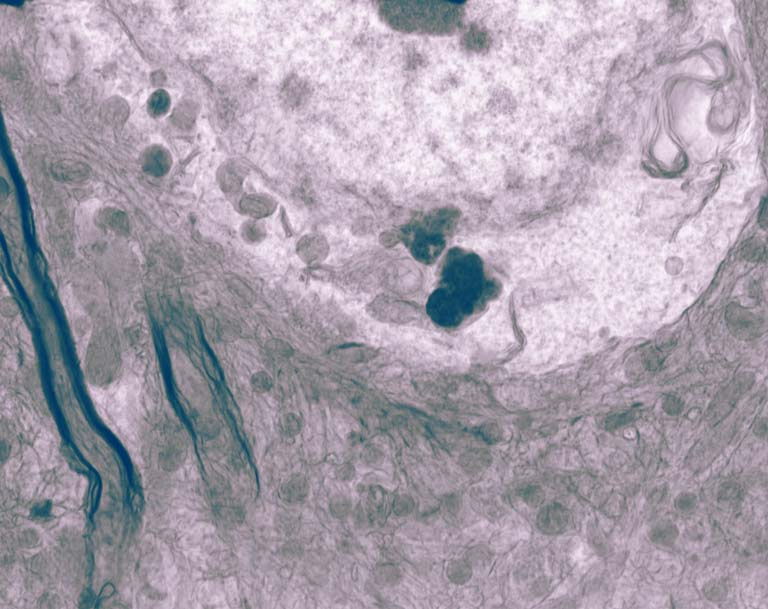

While much is known about processes linked to neurodegeneration in Huntington’s disease, few insights exist for how pathological phenotypes impact organelle structure and function in neural tissue. The Housman Lab uses electron microscopy driven by the expertise and cutting-edge resources of the Nanotechnology Core Facility to visualize and quantify ultrastructural signatures of disease in HD model systems such as the mouse model shown in this image. We aim to learn which organelle structures are the most disrupted in HD. With these signatures, we hope to evaluate if the treatments we are currently developing using human genetics can reverse structural abnormalities present in the HD brain. Colors are added for an artistic effect.